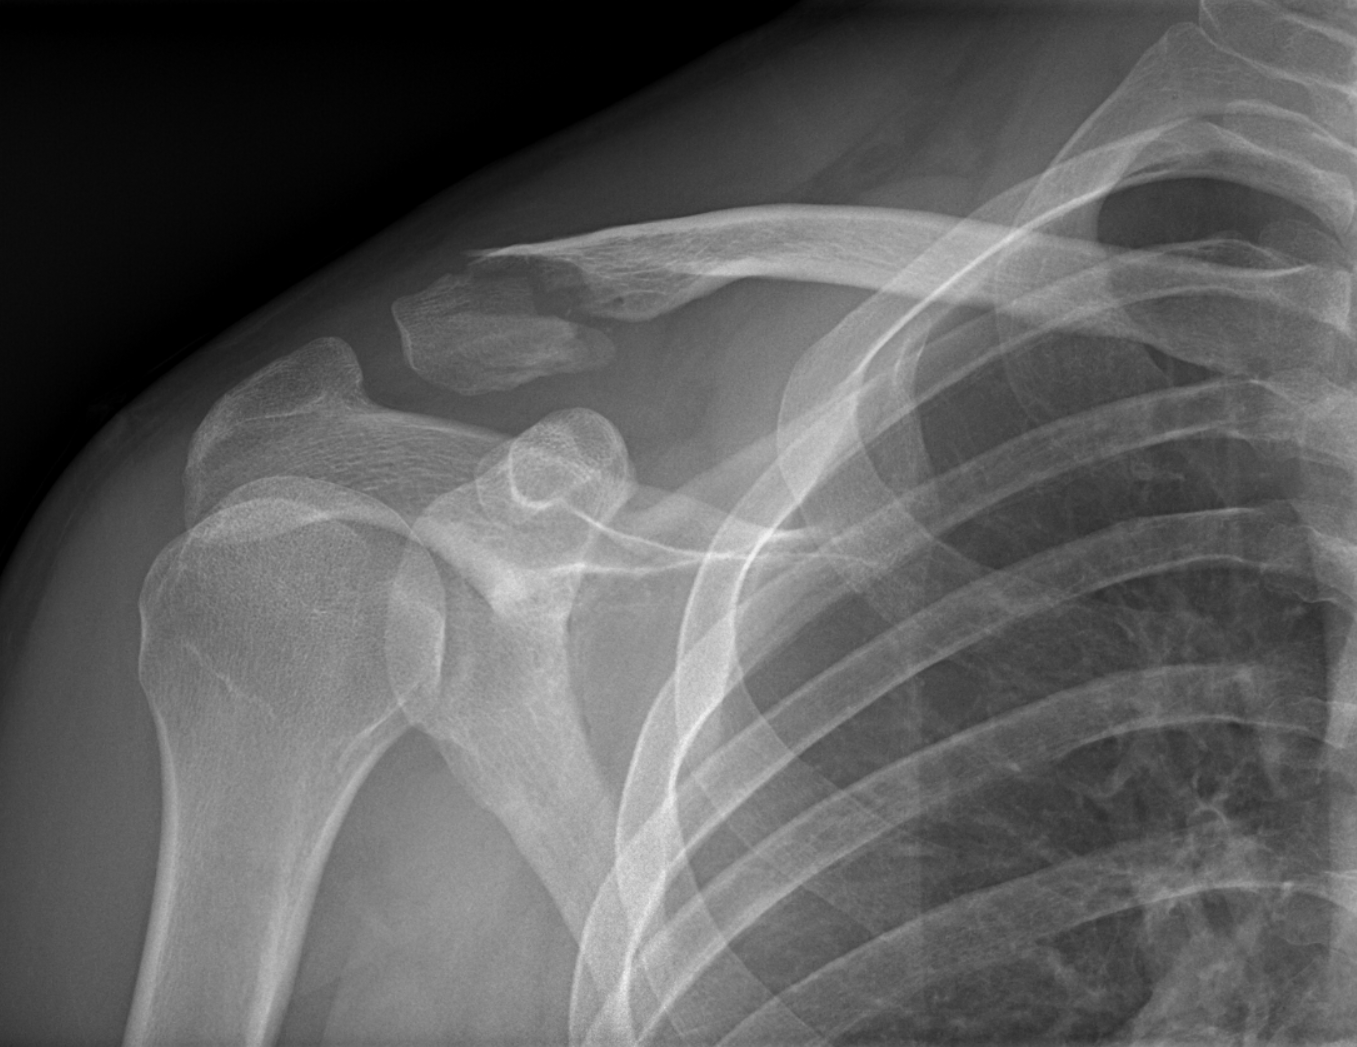

Princip vyšetření je založen na schopnosti rentgenového záření pronikat hmotou a dle vlastností jednotlivých tkání se specificky zeslabovat. Výsledkem je obraz zachycený na citlivý materiál – rentgenový film či detekční systém přístroje. Rentgenové vyšetření se hodí zejména k posouzení kostí a plic. Dále je možné např. z obsahu plynu ve střevech posoudit průchodnost střeva. Na snímcích lze hledat cizí kovová tělesa v těle.

Provádíme kompletní spektrum základních i speciálních skiagrafických vyšetření skeletu i měkkých částí lidského těla.

Ukázky RTG snímků